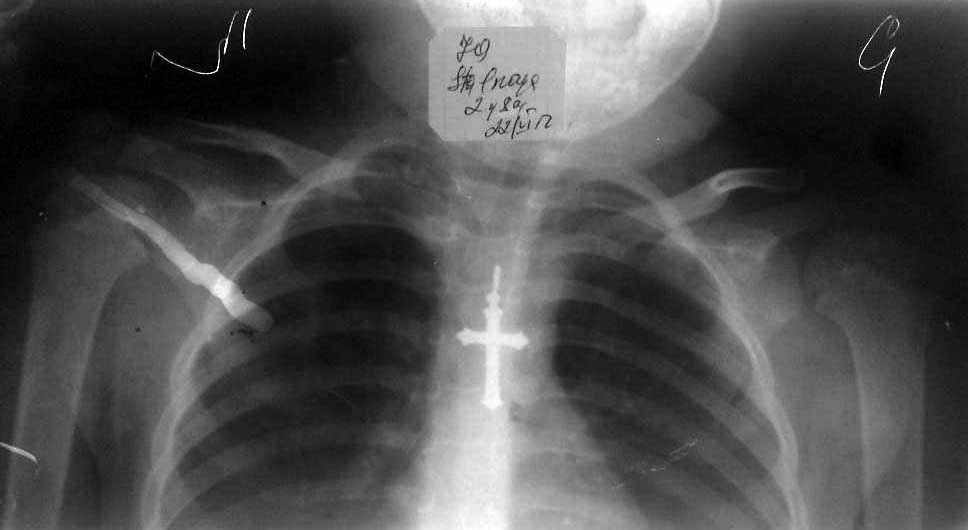

[Ortho] врожденный двухсторонний привычный вывих плеча

вот рентгеннограмма и фото больной